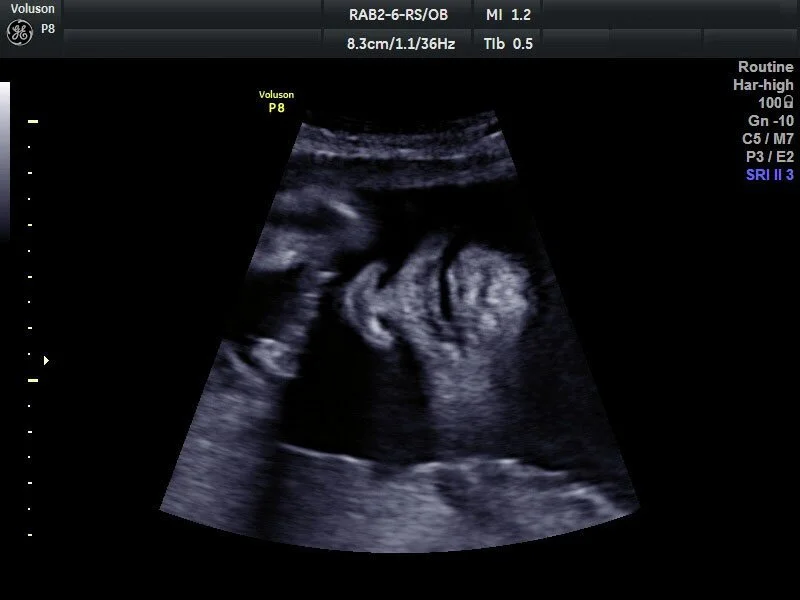

Ультразвуковая диагностика — один из самых безопасных и информативных методов исследования, применяемый в гинекологии, кардиологии, урологии и других областях. УЗИ аппараты позволяют визуализировать внутренние органы, ткани и плод без радиации, что делает их востребованными в клиниках любого уровня. В 2025 году более 80% медицинских центров в Москве используют УЗИ для первичной диагностики.

- Специализированные сканеры. Разработаны для узких областей, таких как кардиология или акушерство.

- Режимы сканирования. 2D, 3D/4D, допплерография расширяют возможности диагностики.

- Определите специализацию. Для гинекологии подойдут аппараты с 3D/4D, для кардиологии — с допплером.